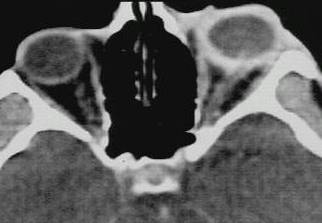

What type of image is it? CT scans or MRI scans (T1 or T2

weighted)

Which plane the image is in? axial, sagittal or coronal.

Describe the image: In ophthalmology, most of the pathology will

be focused on the globe, orbit or the brain. If it were the viva,

ask the examiner for some history.

Examine the following strucutres in order and always compare the

two sides for asymmetry(ies):

globe: eye present (enucleated eye or implant)?

lens present (aphakia)? opacities in the vitreous (blood or foreign body)?

calcification in the retina (retinoblastoma)? calcification in the optic

nerve (drusen)? any abnormal thickening of the sclera (compared with the

opposite eye, thickening suggests scleritis)?